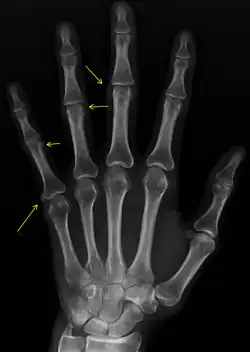

X-ray of subtle calcifications in CREST syndrome

Calcinosis

CREST causes thickening and tightening of the skin with deposition of calcific nodules ("calcinosis").